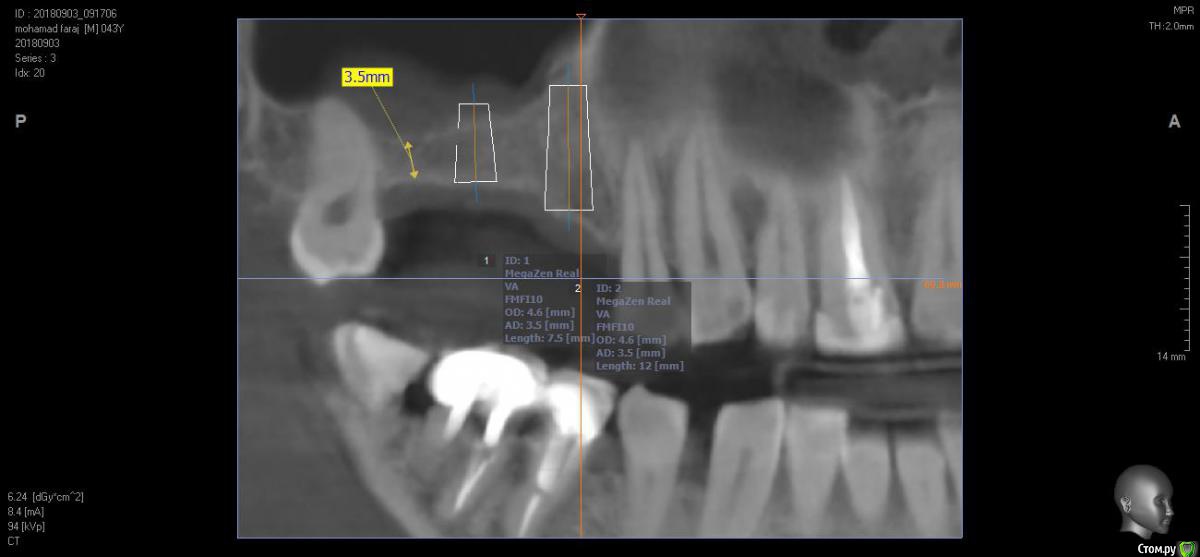

bilal Опубликовано 3 сентября, 2018 Поделиться Опубликовано 3 сентября, 2018 добрый вечер.как вы думате в данной ситуации возможно ли ставить 2 импланта вместо 15 и 16 и соединить одным мостом с зубом 48...пациент против синуслифта.Знаю про все отрицательные моменты соединения зубов и имплантов . Ссылка на комментарий